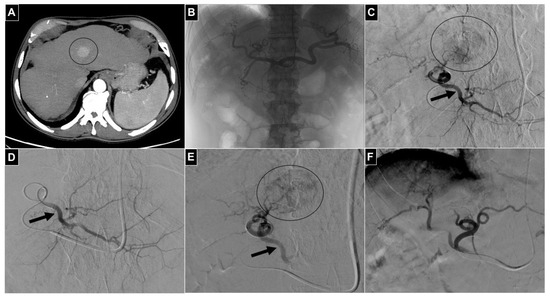

| 10 TACE | 8 HCC 2 CCC | 8 Intrahepatic segmental a. 2 Left gastric a. | Intrahepatic a. | Lipiodol-doxorubicin Preloadable chemiotherapic beads Embocept-S®-doxorubicin |